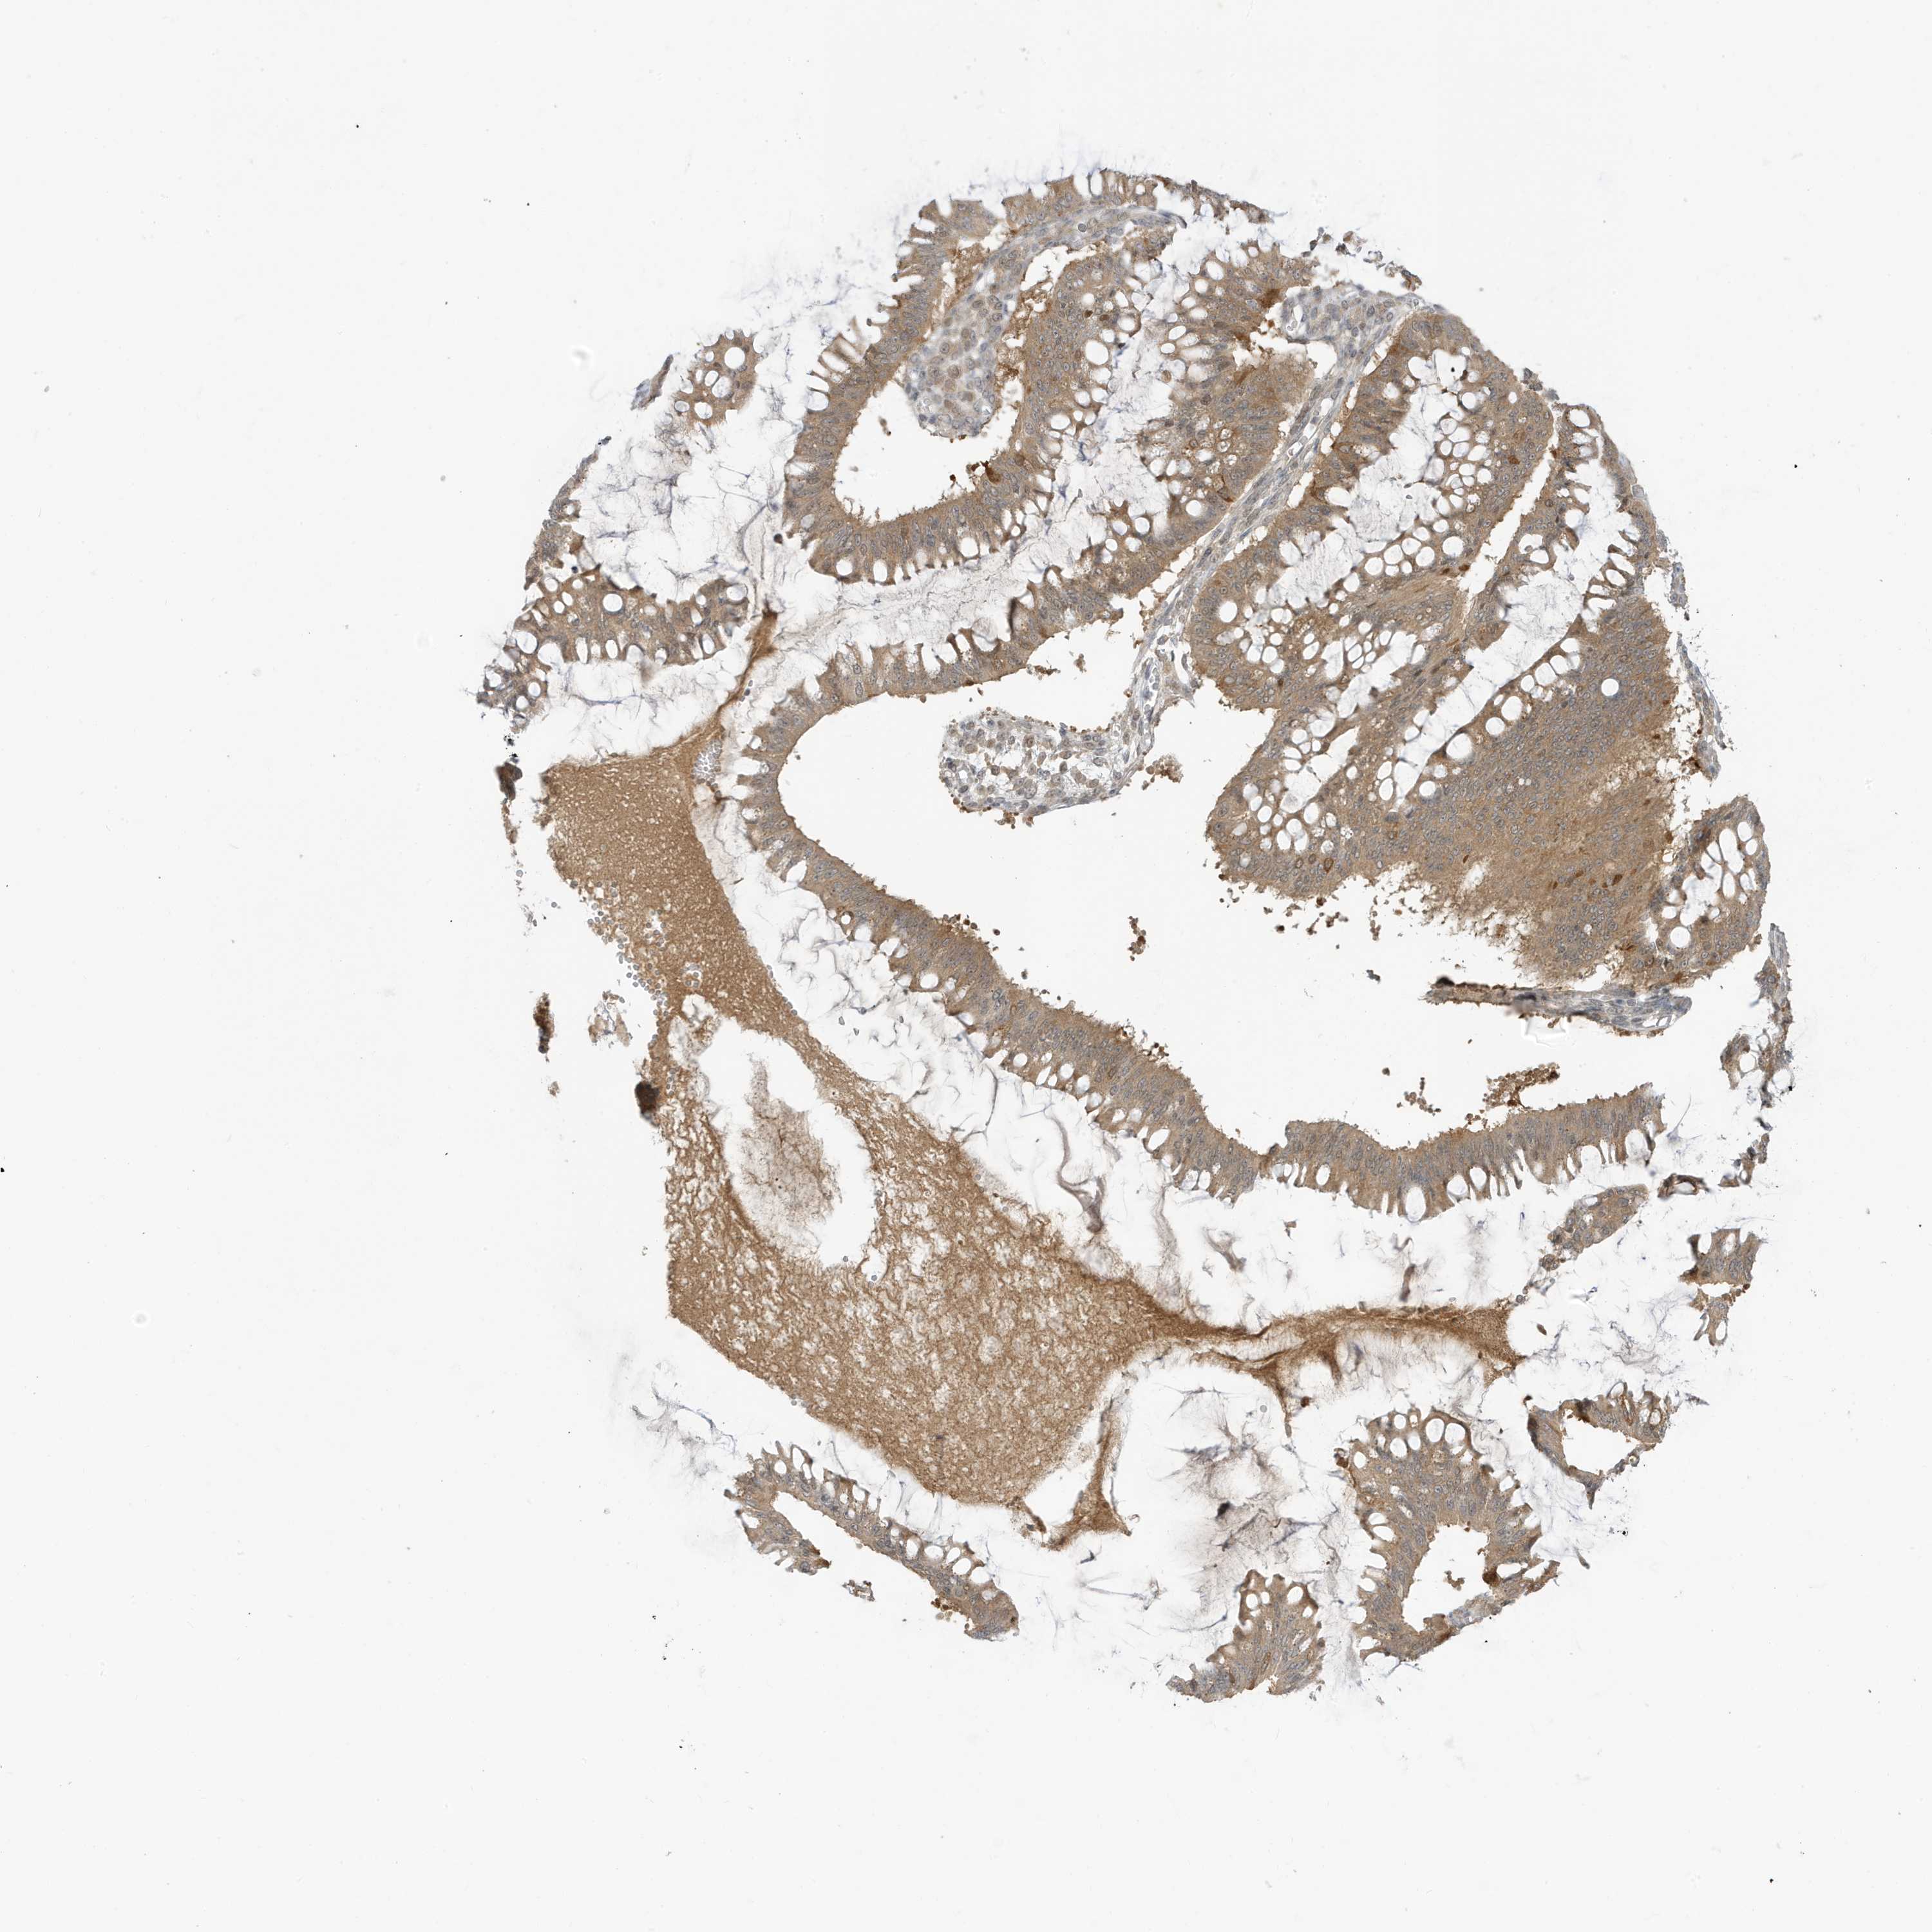

OVARIAN CANCER - Protein expressioni

A mouse-over function shows sample information and annotation data. Click on an image to view it in a full screen mode. Samples can be filtered based on level of antibody staining by selecting one or several of the following categories: high, medium, low and not detected. The assay and annotation is described here.

Note that samples used for immunohistochemistry by the Human Protein Atlas do not correspond to samples in the TCGA dataset.

Antibody stainingi

Antibody staining in the annotated cell types in the current human tissue is reported as not detected, low, medium, or high, based on conventional immunohistochemistry profiling in selected tissues. This score is based on the combination of the staining intensity and fraction of stained cells.

Each image is clickable and will lead to virtual microscopy that enables deeper exploration of all samples and also displays staining intensity scores, fraction scores and subcellular localization as well as patient and tissue information for each sample.

Antibody HPA034980

Antibody HPA034981

Carcinoma, NOS